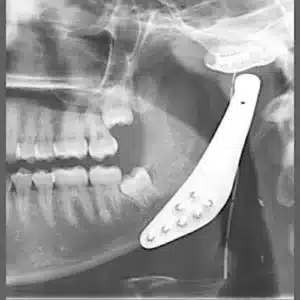

Фото до и после челюстной хирургии в Турции

Результаты коррекции челюсти. Выполнена доктором Эрен Пера в клинике Hospitaprime Dental Clinic.